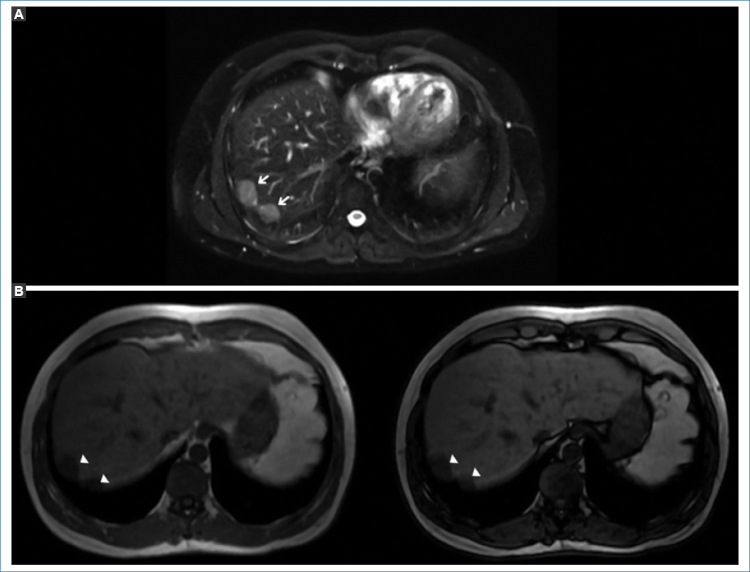

Se decide realizar una resonancia magnética (RM) para mejor caracterización de dichas lesiones, las cuales, junto con las observadas a nivel peritoneal ya descritas anteriormente como esplénulos por su estabilidad en el tiempo, son hipointensas en las secuencias ponderadas en T1, ligeramente hiperintensas en T2 y FATSAT, con tenue restricción de la difusión (DWI) y con similar realce tras la administración del contraste paramagnético (Figs. 2a4).

En los estudios de TC multidetector y RM, el tejido esplénico heterotópico tiene la misma apariencia e igual comportamiento que el bazo tras la administración del contraste endovenoso. En la TC sin contraste, la lesión es isodensa con respecto al parénquima hepático y presenta realce en fase arterial, difícil de diferenciar de un adenoma o un hepatocarcinoma4. En la RM, previo a la administración de contraste paramagnético, la lesión es homogéneamente hipointensa en las secuencias ponderadas en T1 e hiperintensas en las ponderadas en T2; después de la administración del gadolinio es hiperintensa en comparación con el resto del parénquima hepático1,5.